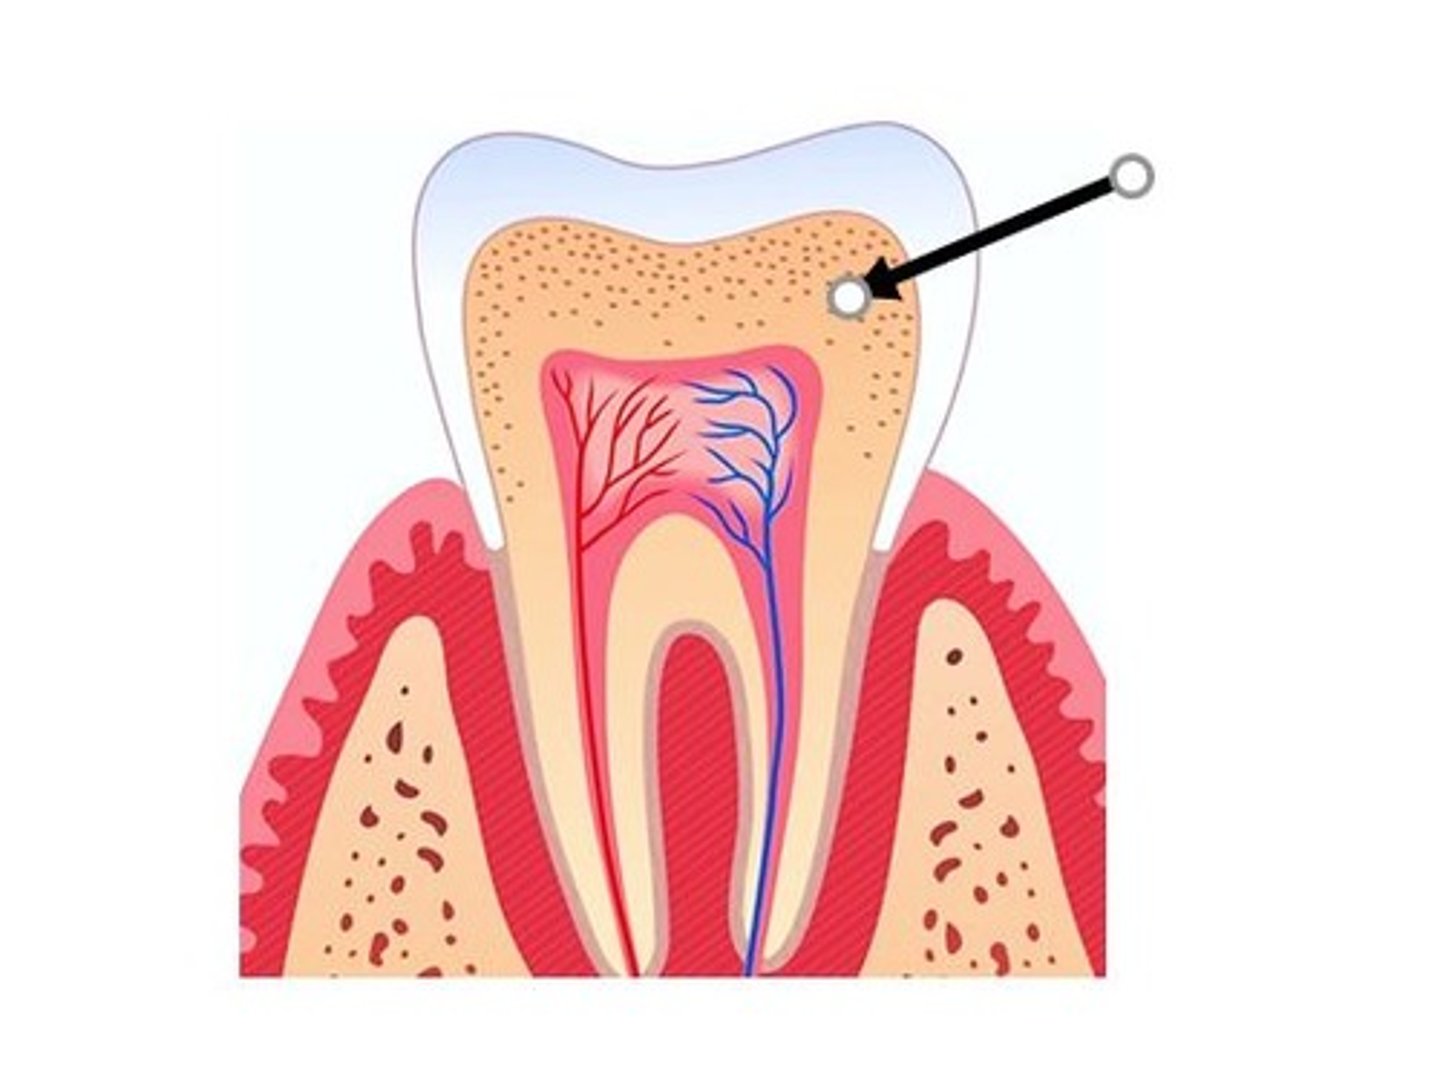

enamel

What tissue of the anatomic crown is this?

<p>What tissue of the anatomic crown is this?</p>

pulp

Which tooth tissue contains

<p>Which tooth tissue contains</p>